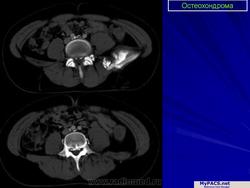

Остеохондрома (костно-хрящевой экзостоз). Это доброкачественный грибовидный отросток, соединенный с помощью костной ножки с подлежащим метафизом. Головка этого грибовидного образования покрыта хрящом. Остеохондрома бывает одиночной и множественной. Последний вариант относится к множественному наследственному экзостозу, который наследуется по аутосомно-доминантному типу. Полагают, что одиночная остеохондрома возникает из-за смещения боковой порции ростковой зоны, которая затем пролиферирует в косом направлении по отношению к оси кости и в направлении от ближайшего сустава. Как правило, такая опухоль обнаруживается в позднем юношеском возрасте или у молодых взрослых лиц (в то время как множественные остеохондромы определяются уже в детстве). По неизвестным причинам мужчины поражаются в 3 раза чаще женщин. Остеохондрома обычно растет от метафиза, локализуясь рядом с ростовой пластинкой длинных трубчатых костей. Иногда опухоль развивается из костей таза, лопаток, ребер. При локализации в указанных губчатых костях остеохондрома, как правило, имеет короткую ножку. Наконец, совсем редко эта опухоль поражает короткие трубчатые кости кистей и стоп.

Остеохондрома - медленно растущее новообразование. При вовлечении в зону ее роста нерва или при переломе ножки опухоли отмечают болезненность. Но часто остеохондрому обнаруживают как случайную находку. При множественных наследственных экзостозах подлежащие кости могут быть искривлены и укорочены, что отражает генетическое нарушение роста эпифизов. В периоде закрытия ростковых пластинок рост остеохондромы обычно прекращается. Однако некоторые ее варианты все же продолжают расти в течение детства пациента. Большинство остеохондром отличается совершенно «безобидным» клиническим поведением. Лишь менее 1 % таких опухолей способны превращаться в хондросаркомы или какие-либо другие саркомы [по Cotran R.S., Kumar V., Collins Т., 1998]. Причем риск малигнизации существенно выше у лиц с наследственным вариантом остеохондромы.

Строение остеохондромы весьма характерно. Опухоль имеет грибовидную форму, ее размеры варьируют в пределах 1-20 см. Наружный слой головки этого новообразования покрыт различной толщины доброкачественным гиалиновым хрящом, ограниченным надхрящницей. Хрящ имеет вид дезорганизованной ростовой пластинки. Оп подвергается энхондральной оссификации, а вновь образованная кость формируется во внутренних частях головки и ножки. Корковый слой ножки опухоли сливается с аналогичным слоем диафиза кости, а костномозговые полости остеохондромы и самой кости сообщаются между собой.

Остеохондрома.